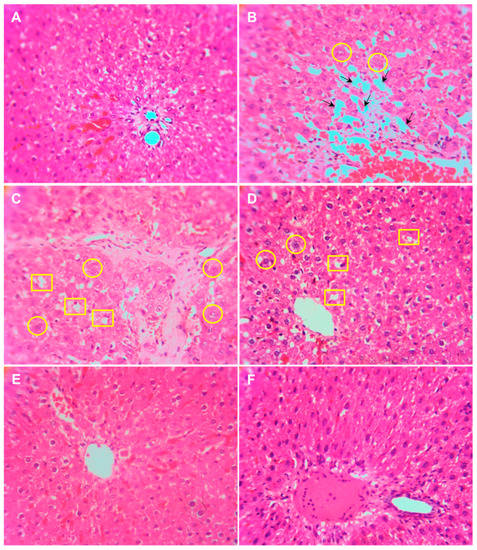

3.5. Histopathology of the Liver